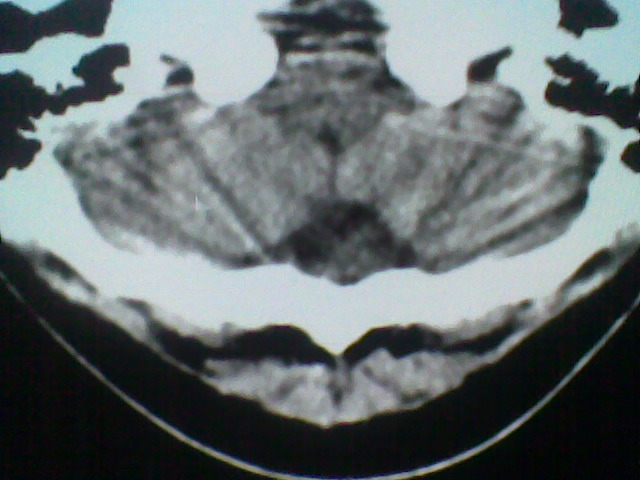

患者,男,头晕4天来诊,要求ct。

大枕大池合并蛛网膜囊肿。

支持 大枕大池合并蛛网膜囊肿。

考虑大枕大池合并蛛网膜囊肿。

有没有dandy-walker综合征的可能?